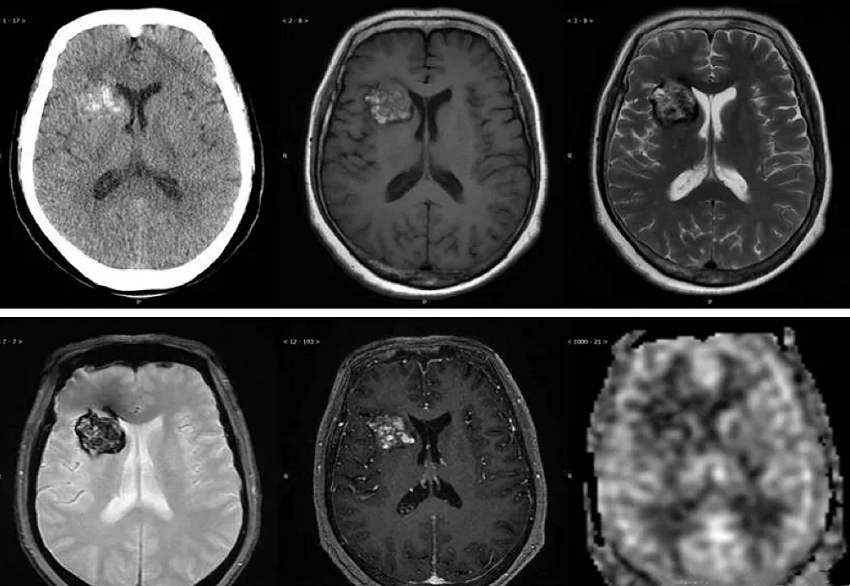

1.脑部CT 脑海绵状血管瘤在CT中典型表现为边界较清楚、密度不均或高密度影,部分病灶伴有钙化;脑部CT检查可能遗漏体积较小的海绵状血管瘤。

2.脑部MRI 脑海绵状血管瘤诊断价值最高的检查;在T2序列上,可见海绵状血管瘤出血形成明确的含铁血黄素沉积低信号带,可见病变呈“爆米花”或“桑葚”样。

脑部CT和MRI检查可明确海绵状血管瘤的位置并对其进行分型并预测其生物学行为;例如分叶状的海绵状血管瘤,既往常有出血史,该类海绵状血管瘤再出血风险高。